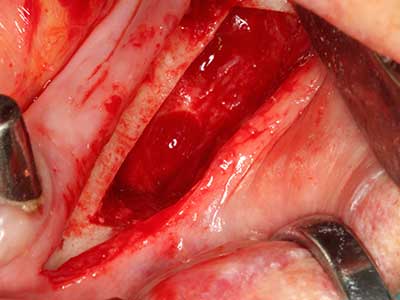

Aplicación: Preparación cerca del nervio

Como ya se ha mencionado, en el ámbito de la odontología conservadora también existen áreas en las que está indicada la cirugía piezoeléctrica. El uso de insertos de trabajo especiales facilita la representación del ápice radicular y, sobre todo en el área de los premolares inferiores y superiores, protege mejor los nervios y las mucosas del seno maxilar. En el caso de un cierre apical no estanco, los insertos de diamante acodados preparan de forma exacta y selectiva la cavidad de resección para el material de relleno retrógrado de la raíz. Gracias a la técnica de ultrasonidos, los insertos pueden presentar un diseño muy estilizado, lo que mejora la visión global y el tamaño de la cavidad de acceso. De este modo, en esta indicación, el uso de la cirugía por ultrasonidos se encuentra entre los métodos estándar para una apicectomía (Del Fabbro, Tsesis et al. 2010, Scarano, Artese et al. 2012).

Si es preciso realizar intervenciones quirúrgicas en las que el hueso está en contacto directo con estructuras sensibles, como son los vasos sanguíneos o los nervios, los instrumentos rotativos presentan un enorme potencial de provocar lesiones iatrogénicas. Así, precisamente en la representación de nervios después de una lesión iatrogénica, o en el transcurso de la lateralización de un nervio para resecciones, reconstrucciones o incorporación de implantes, los equipos piezoeléctricos pueden resultar muy útiles para preparar la tapa ósea y retirar las partes de tejido duro cercanas al nervio (fig. 17-20). Por lo general, un ligero contacto del cordón nervioso con el inserto piezoeléctrico no tiene consecuencia alguna; ahora bien, un procedimiento poco cuidadoso con movimientos tipo sierra o piezas de trabajo sobre la base ósea aún existente puede provocar lesiones nerviosas temporales o incluso permanentes. Con todo, el riesgo de sufrir una lesión de este tipo se considera significativamente inferior que en los casos en los que se utilizan sierras y fresas (Pereira, Gealh et al. 2014).